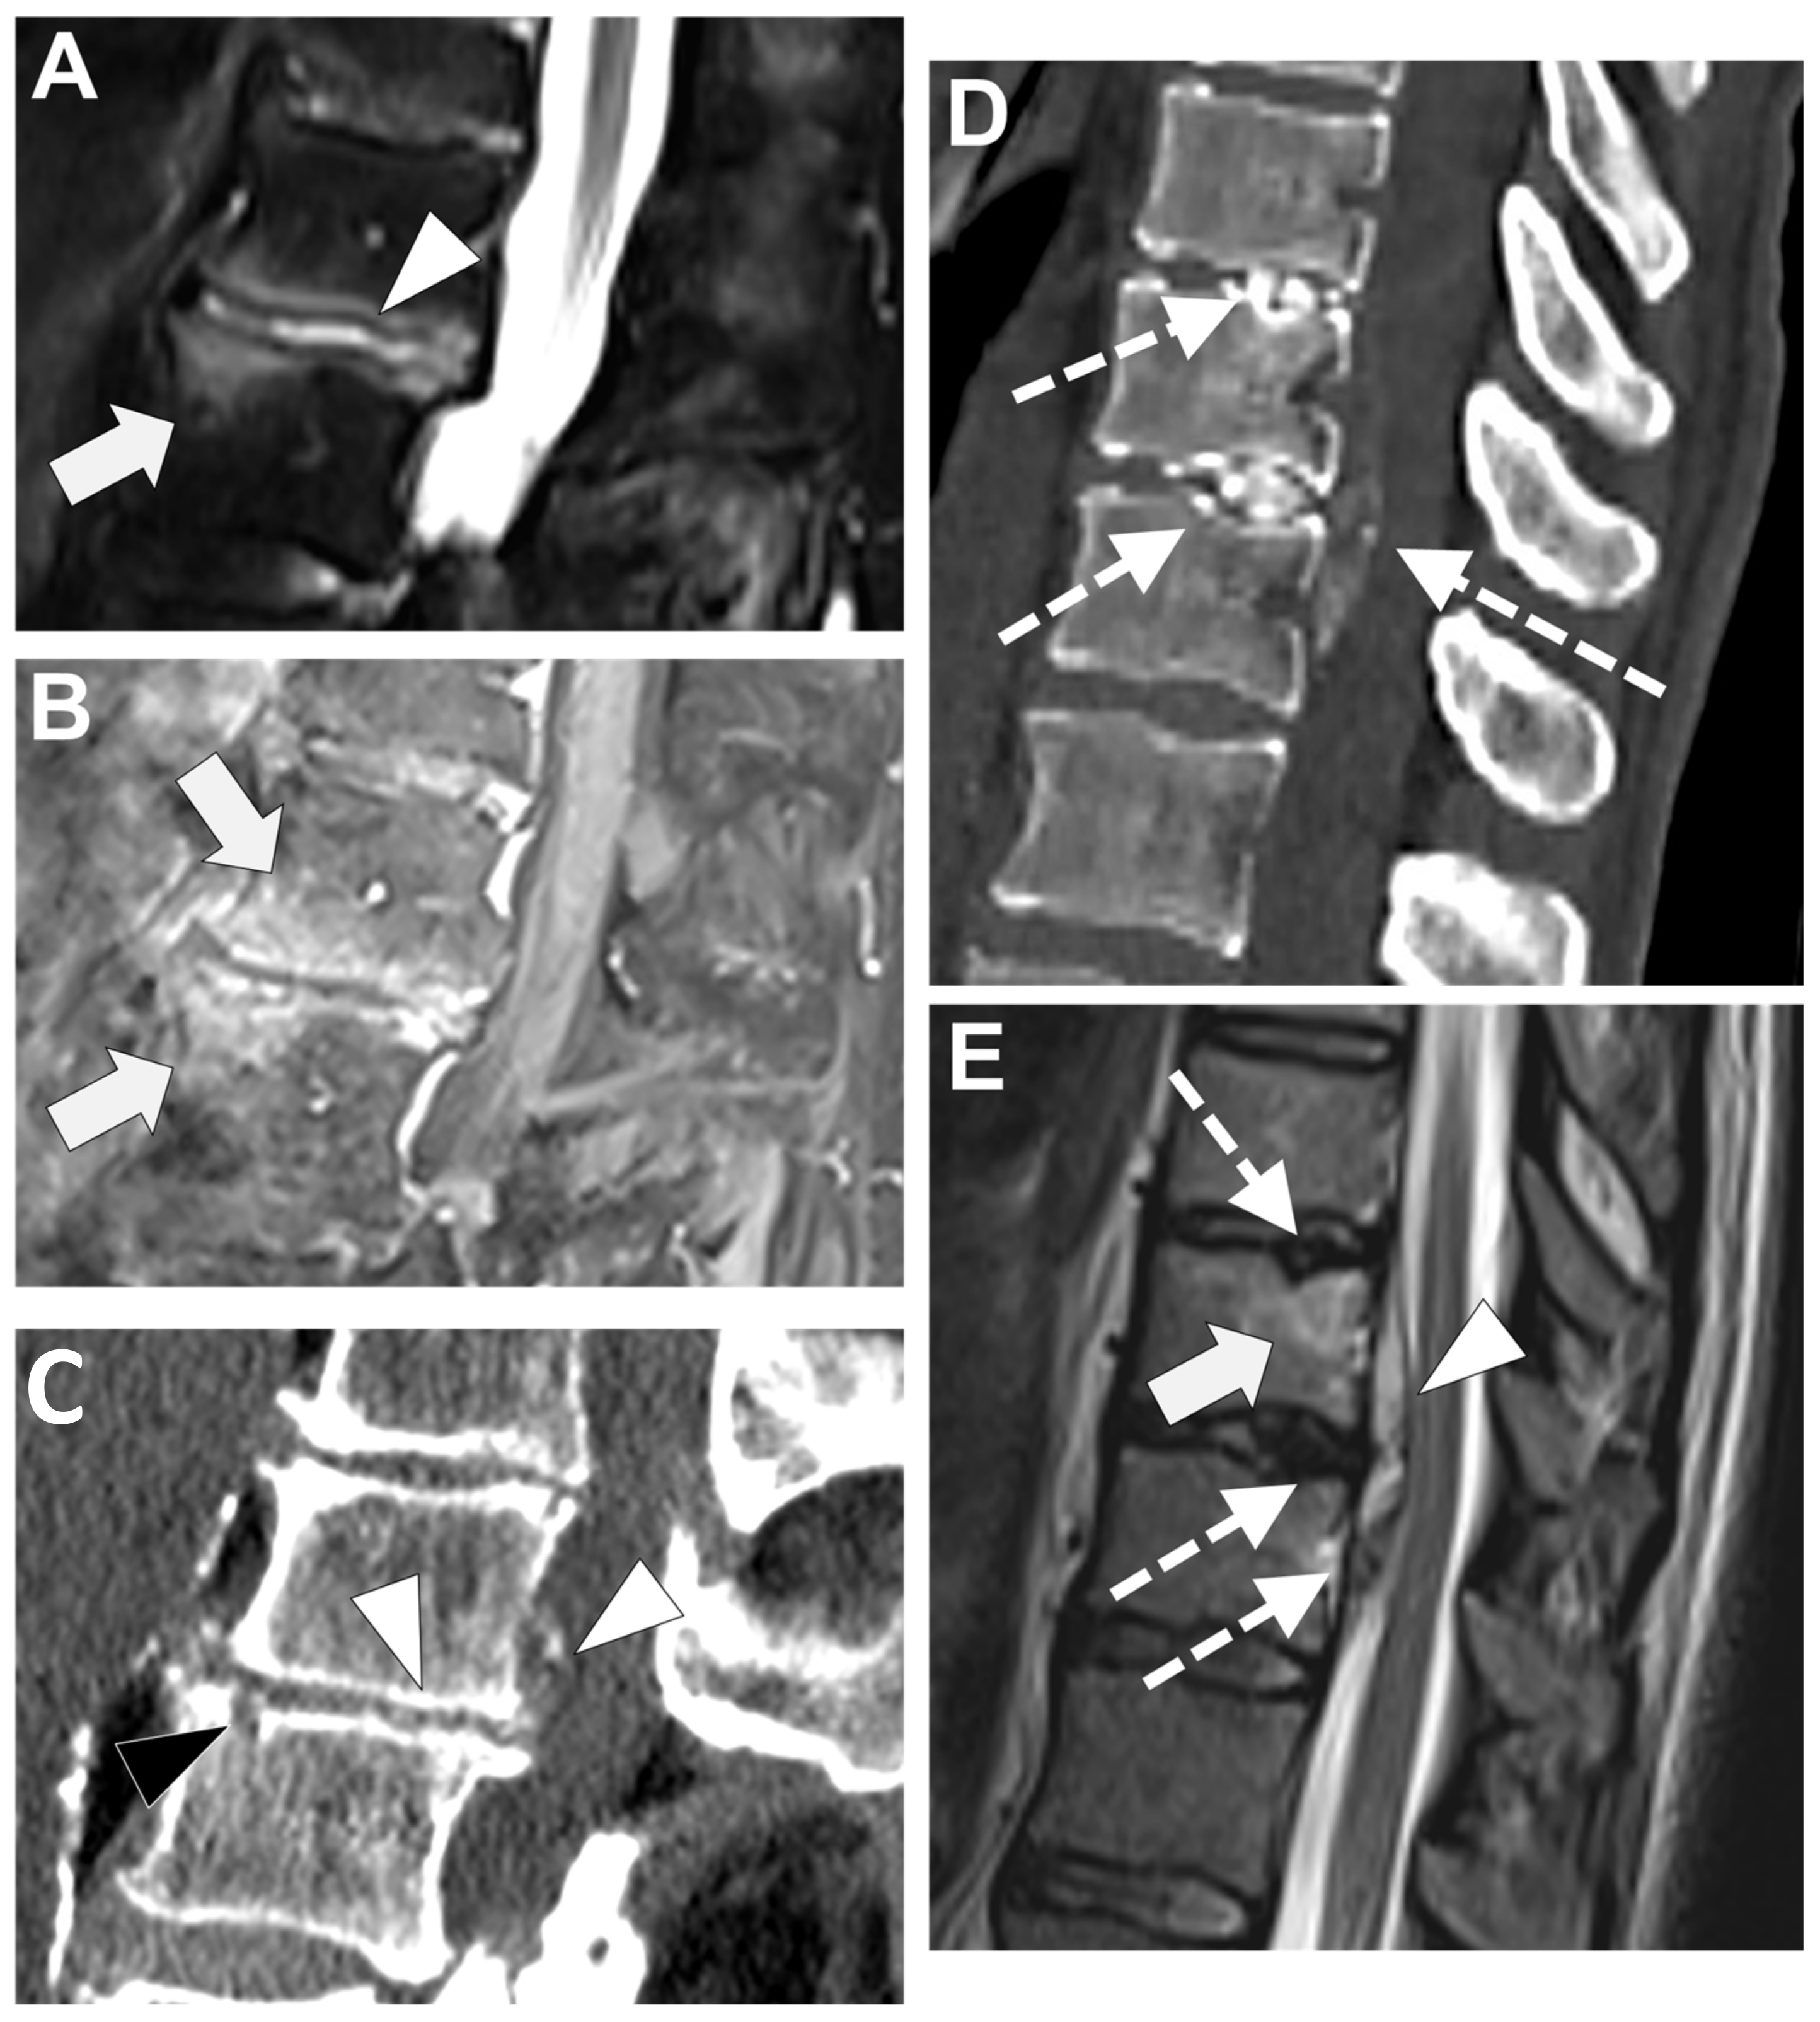

Degenerative end plate changes at the early inflammatory phase (Modic 1) can demonstrate some similar radiological features with infectious spondylodiscitis [72,73], that is to say, irregular end plate contours, possible subchondral cysts, and vertebral edema with a horizontal orientation (with high signal intensity on T2-WI—more pronounced with fat suppression method, low signal intensity on T1-WI, and, when performed, possible contrast-enhancement)—Figure 9.

Figure 9. A 56-year-old male presented with a chronic and mechanic lumbar pain. An MRI was performed with (A) T1-weighted imaging (WI), (B) T2-WI, and (C) fat suppressed T2-WI. It demonstrates multiple Schmorl nodes (arrowheads) and a linear high signal intensity (SI) of the subchondral bones on both side of the L2-L3 level (arrows). There was no erosion, small anterior osteophyte, and degenerative disks. Hence, Modic 1 was diagnosed.